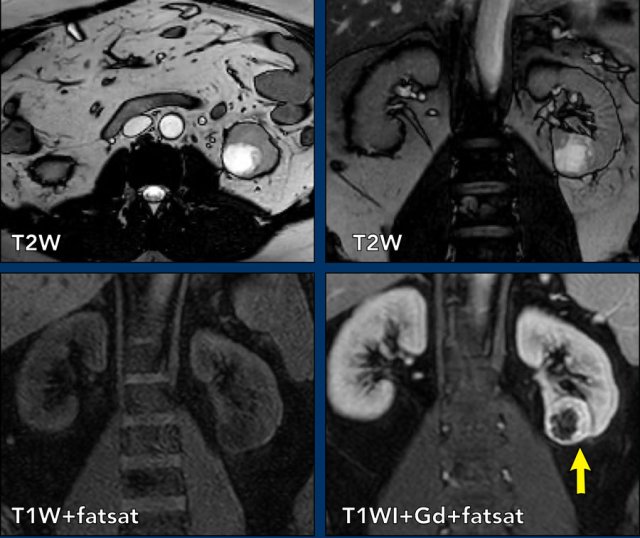

Axial T2WI and coronal T1WI with fatsat and Gadolinium.

There is a cystic mass in the left kidney with many thin enhancing septa.

The lesion is classified as Bosniak IIF.